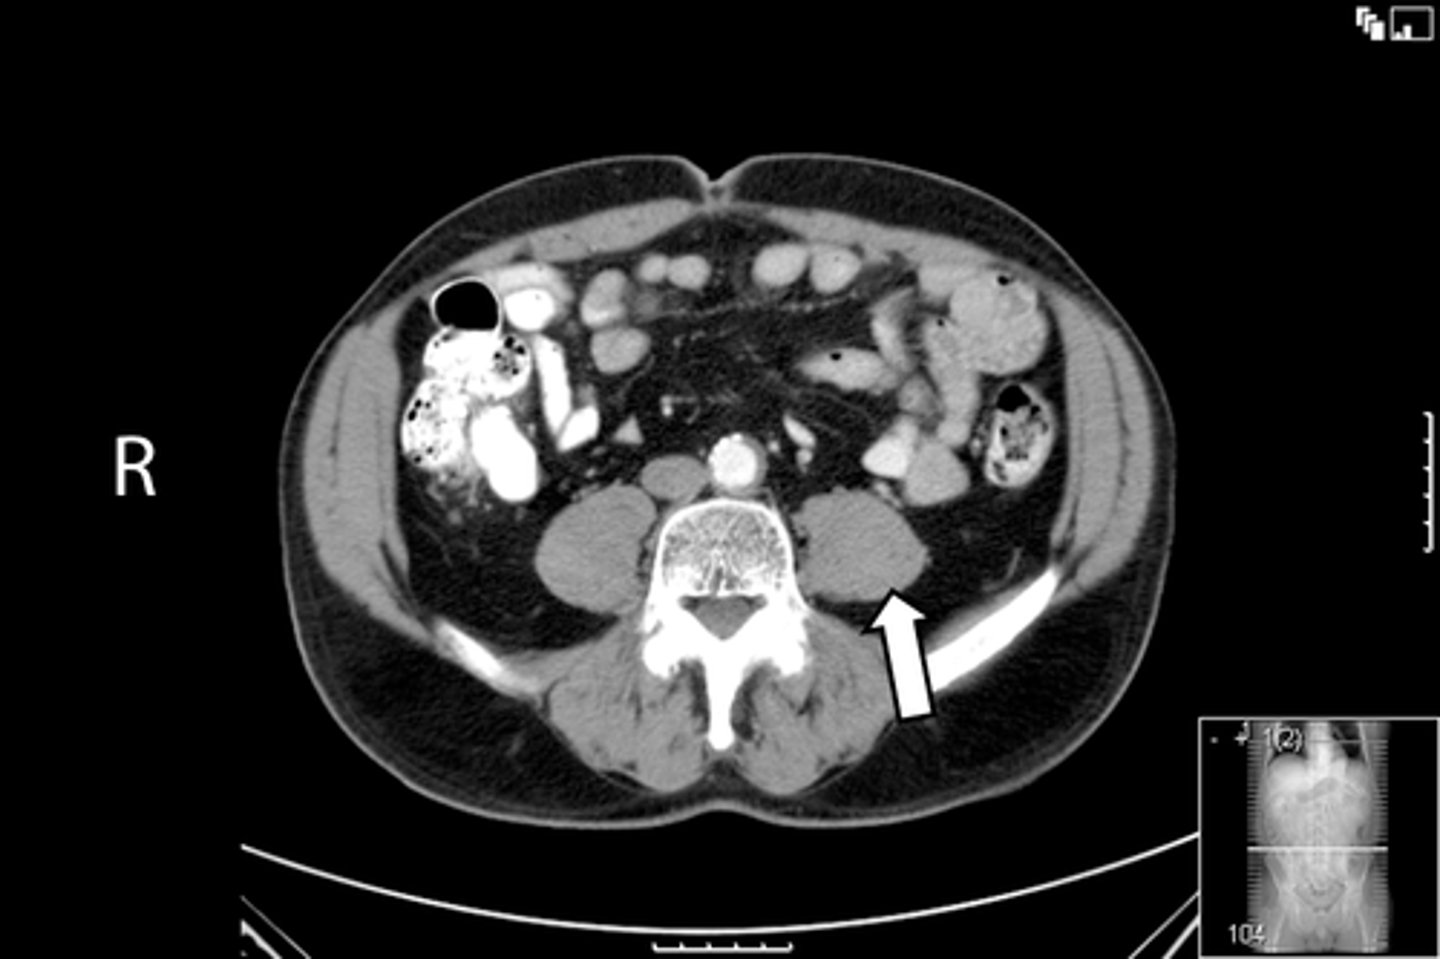

<p>What is indicated in the image?</p>

Axial male pelvis CT

What is the image?

<p>What is the image?</p>

55

New cards

Aorta

What is indicated in the image?

56

Cecum

57

IVC

58

L ilium

59

L psoas muscle

60

R ilium

61

R psoas muscle

62

R rectus abdominis

63

Terminal ilium